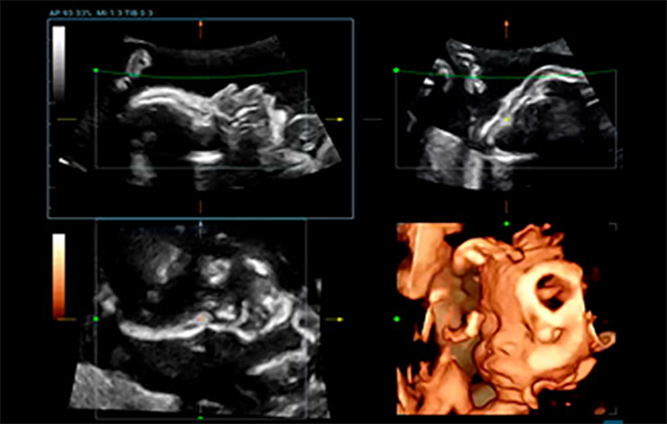

Afin de rĂŠduire la dĂŠpendance Ă l'utilisateur et d'amĂŠliorer l'efficacitĂŠ du diagnostic, Mindray a dĂŠveloppĂŠ une interaction?3D/4D innovante basĂŠe sur des scĂŠnarios cliniques d'examen ĂŠchographique?3D tels que le cerveau, le visage, la colonne vertĂŠbrale et les os longs du f?tus, ce qui permet d'automatiser l'identification de la vue, l'optimisation de l'imagerie, l'acquisition des plans et la quantification en un seul clic. Le flux de travail est vĂŠritablement automatique tout au long de la procĂŠdure, et apporte une grande confiance envers le diagnostic pour de meilleurs soins au patient.

Smart Face